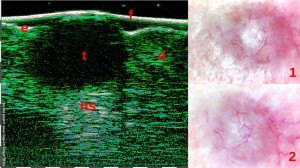

Η διαφοροποίηση μεταξύ των Υπερτροφικών Ουλών (1η εικόνα) και των Χηλοειδών (2η εικόνα) με τη βοήθεια του Υπέρηχου Υψηλής Συχνότητας.

Η εξέταση ακμής με HFUS είναι χρήσιμη για την ακριβή διάγνωση της μορφής της ακμής (φλεγμονώδης/μη φλεγμονώδης, φλυκταινώδους, συγκεντρωτικής ή συνδεσμικής κτλ).

Για παράδειγμα, η σοβαρότητα της ακμής πολύ συχνά υποτιμάται, επειδή οι εσωτερικές αλλαγές στο χόριο είναι αόρατες. Η εξέταση HFUS επιτρέπει την ανίχνευση των σημείων διήθησης, εξίδρωσης και ίνωσης, γεγονός που επιτρέπει τη διάγνωση του τύπου της ακμής και την εφαρμογή της κατάλληλης θεραπείας, με έλεγχο της αποτελεσματικότητας της θεραπείας με HFUS.

Φλύκταινες (1η εικόνα) και συνδυασμός οζιδίων και κυστών (2η εικόνα). Οι πιο έντονες αλλαγές εντοπίζονται στο πάχος του χορίου. Σαρώσεις με Υπέρηχο Υψηλής Συχνότητας και Βιντεοδερματοσκοπικές απεικονίσεις.